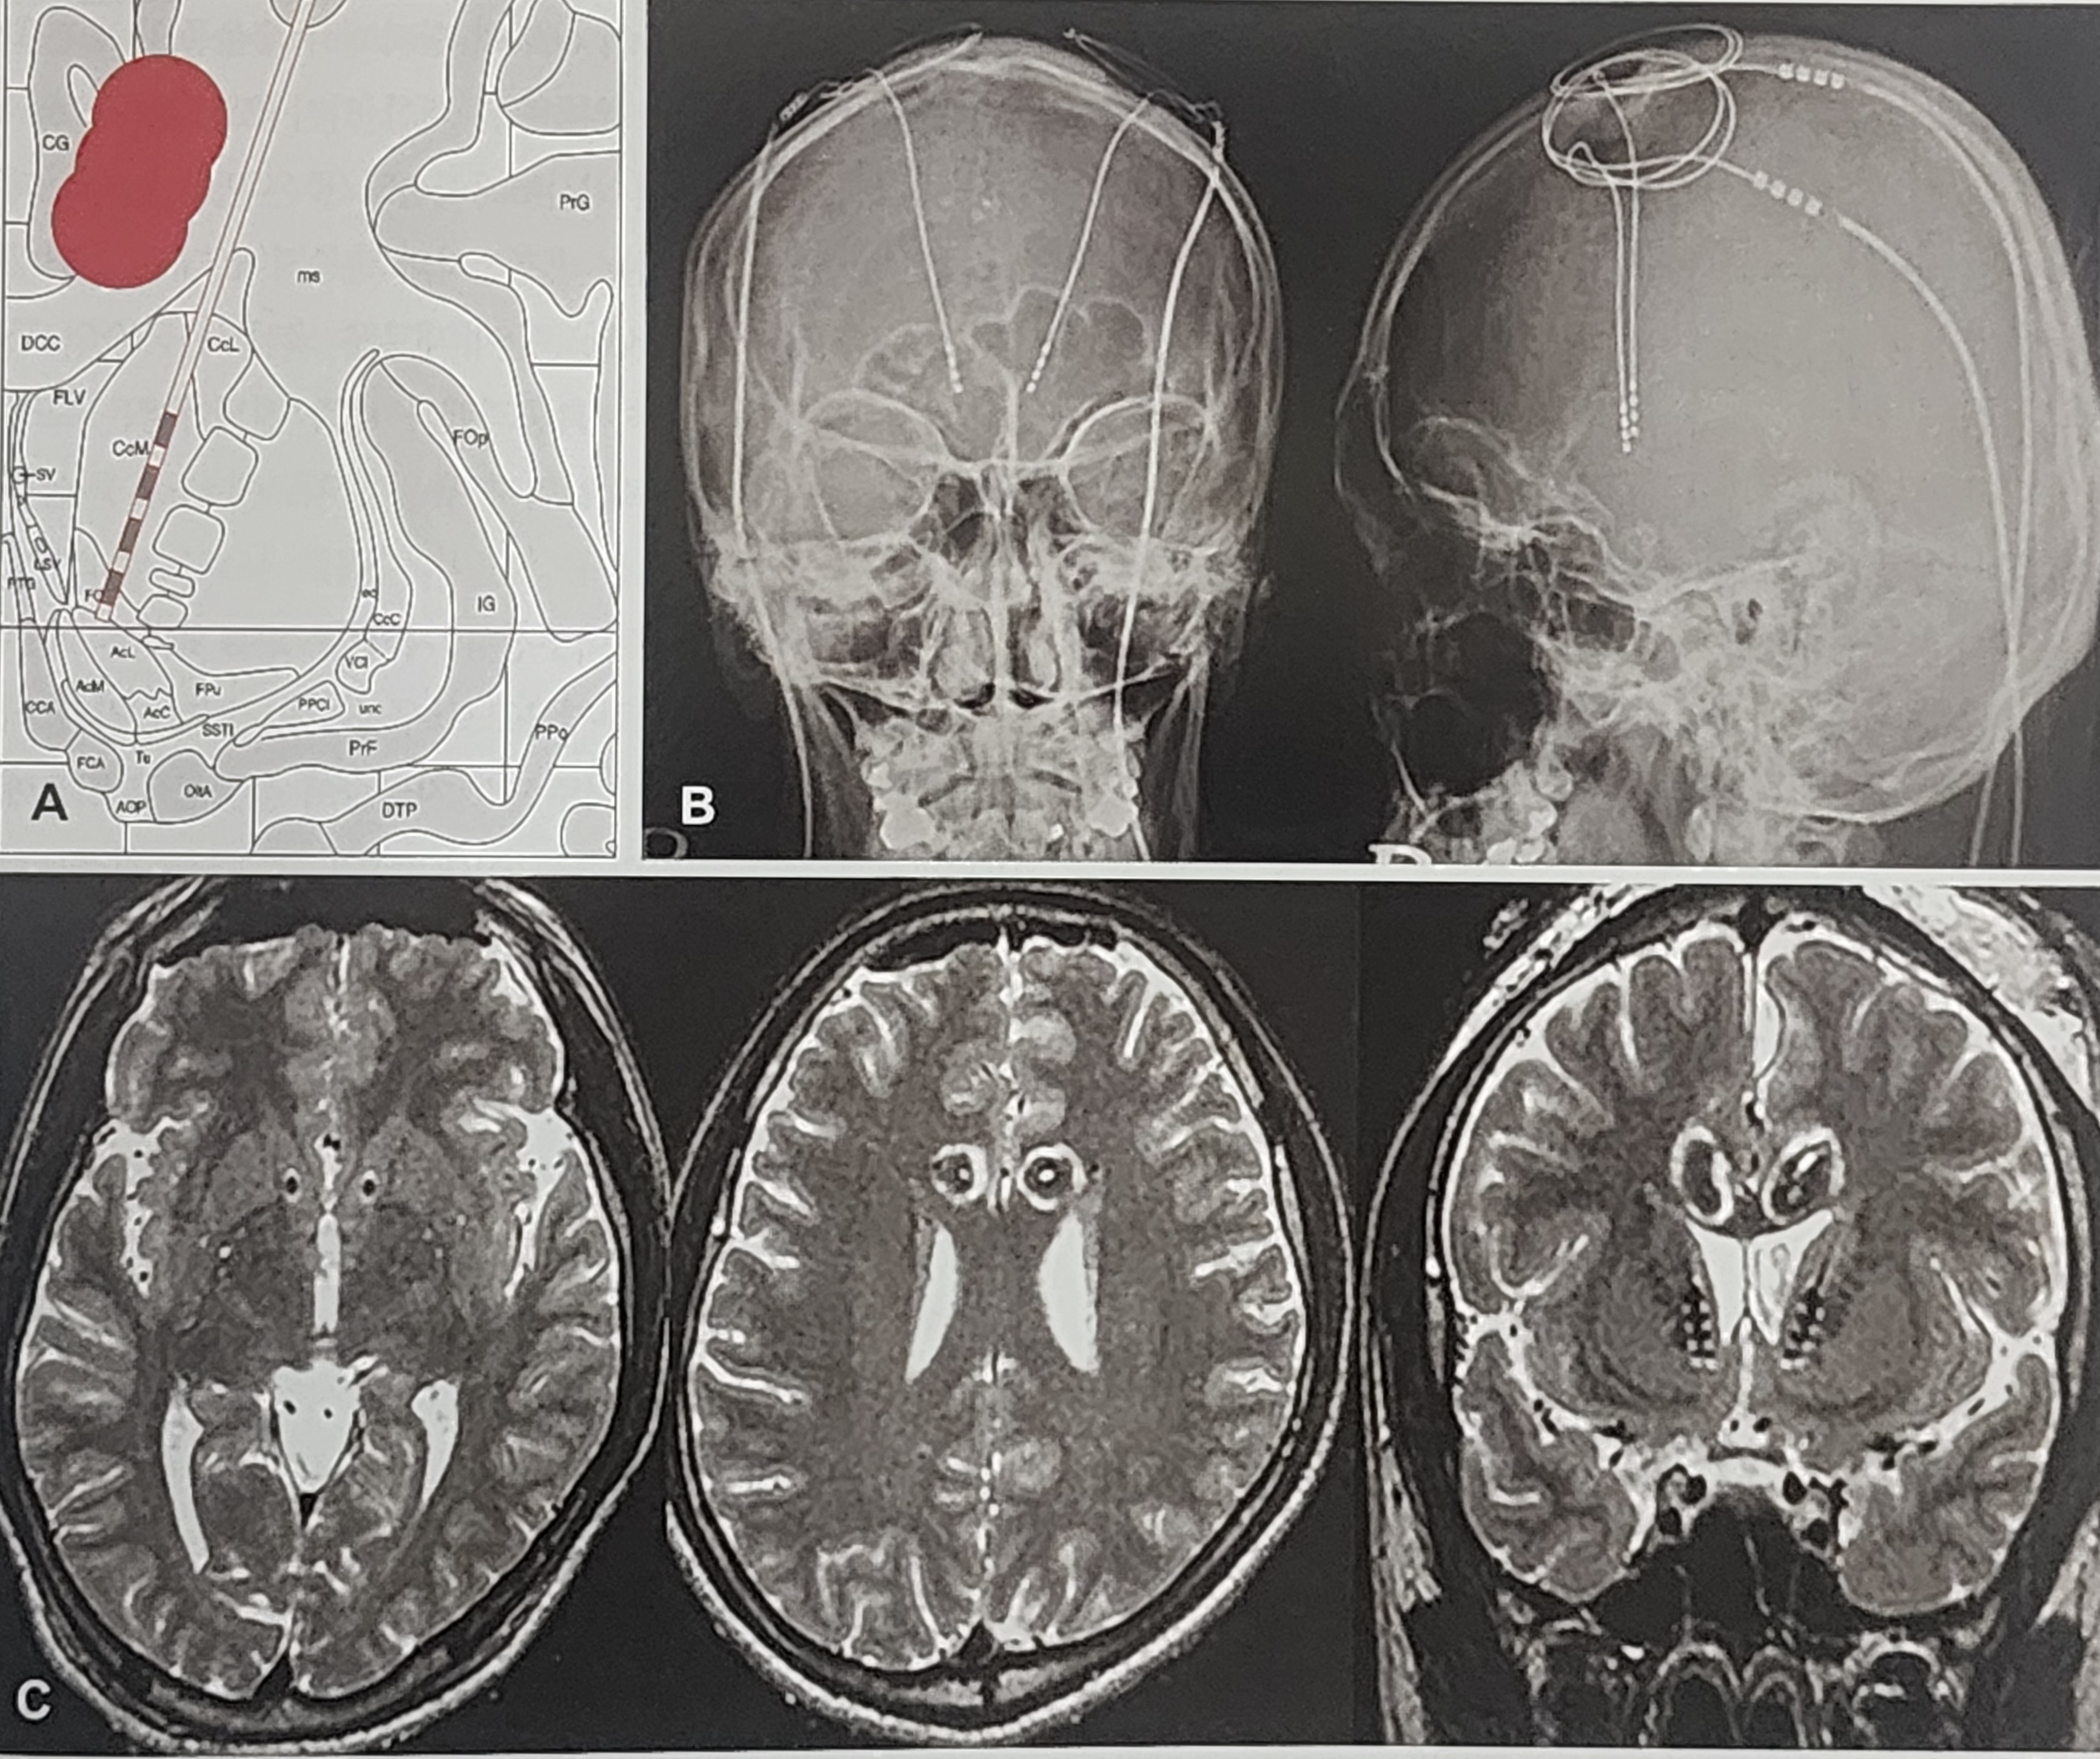

뇌심부자극술(Deep Brain Stimulation, DBS)은 비교적 최신 치료법으로, 강박장애 환자들에게 점차 적용되고 있다.

- 수술 방식: 뇌의 특정 부위(예: 시상하부, 선조체 등)에 전극을 삽입하여 전기 자극을 가하는 방식

- 조절 가능성: 비가역적인 절개술과 달리, 전기 자극의 강도를 조절할 수 있어 상대적으로 안전

- 효과: Yale-Brown Obsessive Compulsive Scale(Y-BOCS) 점수가 35% 이상 감소

DBS는 현재 강박장애뿐만 아니라 우울증, 뚜렛증후군 등의 치료에도 사용되고 있으며, 장기적인 효과 연구가 지속적으로 진행 중이다.